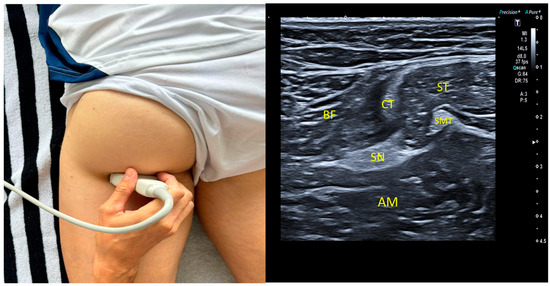

2.5. Ultrasound Imaging Procedure: Sciatic Nerve

2.7. Mid-Third Measurement